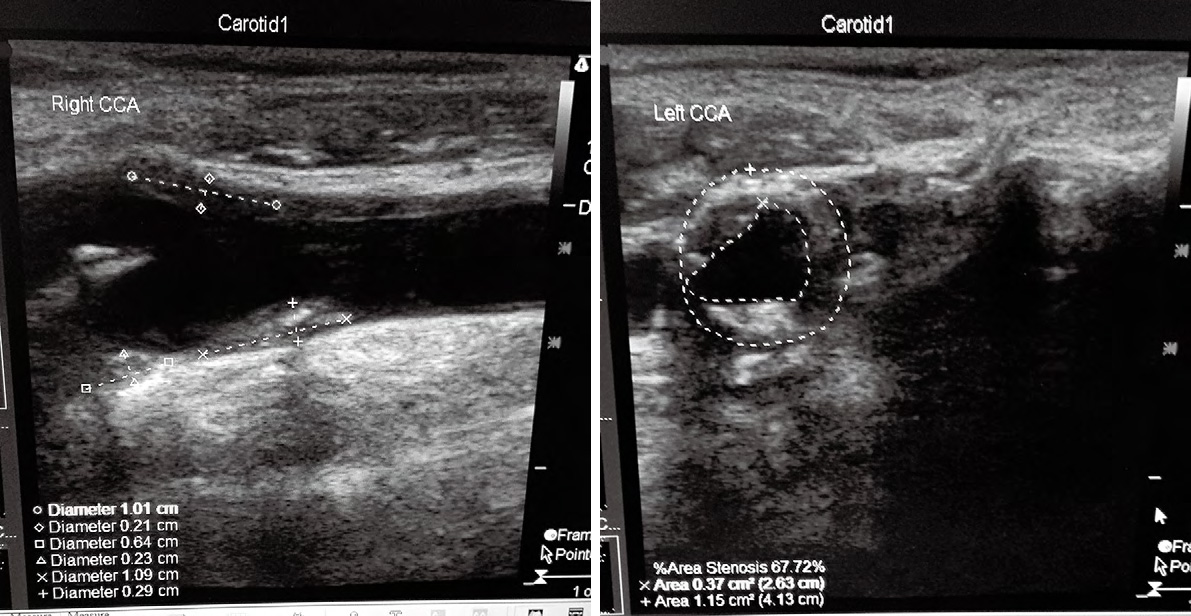

1、2114例患者中的典型病,老年男,主訴為頭昏伴雙手麻木不適數(shù),加重1周來(lái)我院神經(jīng)科門診就,TCD和頸動(dòng)脈超聲聯(lián)合檢查進(jìn)行早期篩查。檢查結(jié)果如下:

1TCD示:雙側(cè)頸內(nèi)動(dòng)脈末-大腦中動(dòng)脈流速顯著增快伴頻譜紊亂,渦流形成, 考慮雙側(cè)頸內(nèi)動(dòng)脈末-大腦中動(dòng)脈狹窄;壓頸試驗(yàn)后證實(shí)右側(cè)大腦前動(dòng)脈、雙側(cè)大腦后動(dòng)脈代償;腦血管彈性減退

2 頸動(dòng)脈超聲提示:雙側(cè)頸動(dòng)脈及椎動(dòng)脈硬化;雙側(cè)頸部數(shù)個(gè)多發(fā)性動(dòng)脈粥樣硬化斑塊形成;右側(cè)頸總動(dòng)脈球部斑塊處管腔輕度狹窄;左側(cè)頸總動(dòng)脈球部斑塊處管腔中度狹窄